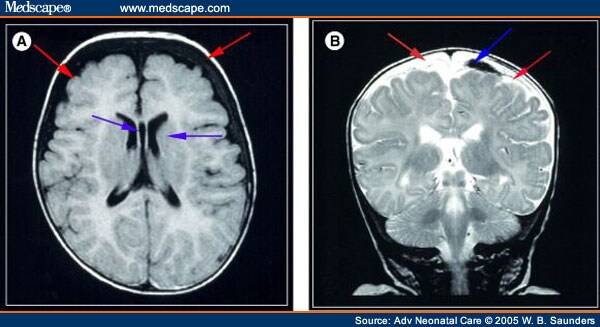

View Baby Brain Bleed Causes Pics. After a brain bleed, a blood vessel can spasm and narrow. They can be caused by birth asphyxia (oxygen deprivation during or around the time of birth) or birth.

Bleeding within the brain can also raise the pressure inside the skull to dangerous levels. They can be caused by birth asphyxia (oxygen deprivation during or around the time of birth) or birth. However, a nasty fall from a height or even from the stairs can lead to bleeding within the brain.

A brain bleed is a medical emergency that needs hospital treatment. The eight infants all had a rare disorder called vitamin k deficiency bleeding, or vkdb which is dangerous but totally preventable with simple (and safe) vitamin k injections given shortly after birth. This occurs when the veins that bridge from the brain to the dura are stretched beyond their elasticity, causing tears and bleeding. A brain bleed is a medical emergency that needs hospital treatment.